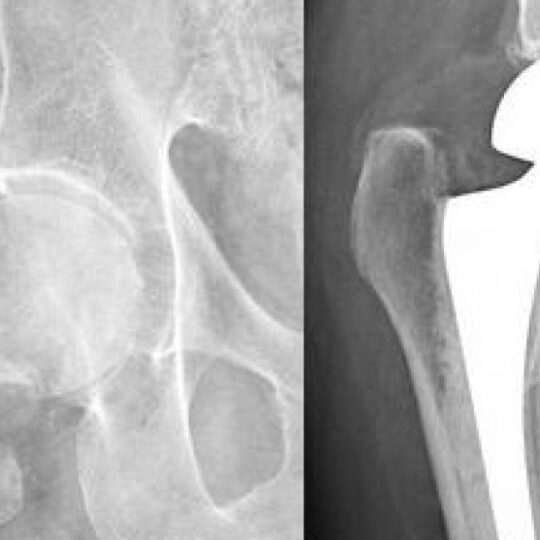

Right Hip Bone Lateral View Diagram Quizlet

Right Hip Bone Lateral View Diagram Quizlet Hip Fracture Nclex Questions Quizlet Fractures, or create your own quiz using our free cloud based quiz maker. We want to make sure the bone gets realigned because displaced. A patient with a hip fracture has petechiae on their chest, dyspnea, and a decrease in oxygen saturation. Anatomy and physiology of the musculoskeletal system, nursing care management of patients with osteoporosis, rheumatoid arthritis, gout, osteoarthritis,. Hip Fracture Nclex Questions Quizlet.